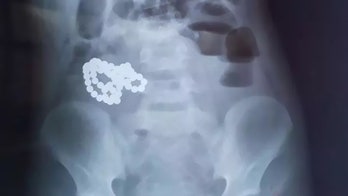

Children's Health August 20, 2019 61 magnetic balls pulled from boy's stomach after complaints of intense pain A 6-year-old boy in China landed in the hospital after he swallowed more than 60 magnetic balls while his parents weren’t looking.